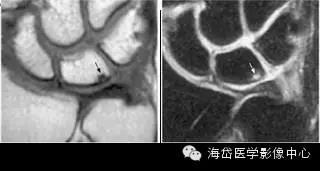

②MRI:MRI对骨髓变化敏感,在骨损伤早期就能反映出骨髓水肿性改变,可做到早期诊断。

随压迫时间延长MRI可见高信号(T2WI)逐渐增强,并形成透镜样改变,晚期形成“双线”或“双环”征。“双环”征提示坏死区内可能有新骨形成,“双线”征表明骨坏死区有瘢痕组织形成。